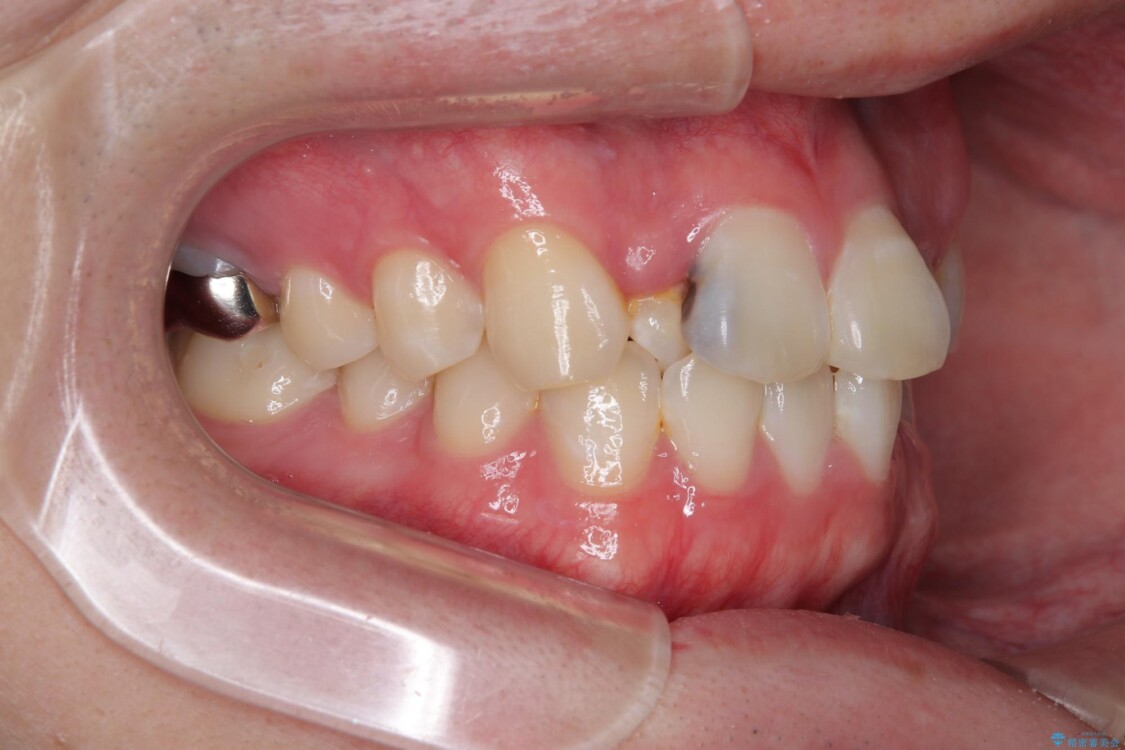

初診時の状態

・上下ともに歯がきれいに並びきらず、がたつきが見られました。

・上下の前歯の中心(正中)がずれています。

・特に上顎の幅が狭いため、下顎の歯列も内側に入り込み、歯が並ぶスペースが不足していました。

治療前

• 1年でここまで変わる!歯列のがたつきと正中のズレを改善した矯正治療(メタルブラケット×MARPE) 治療前画像